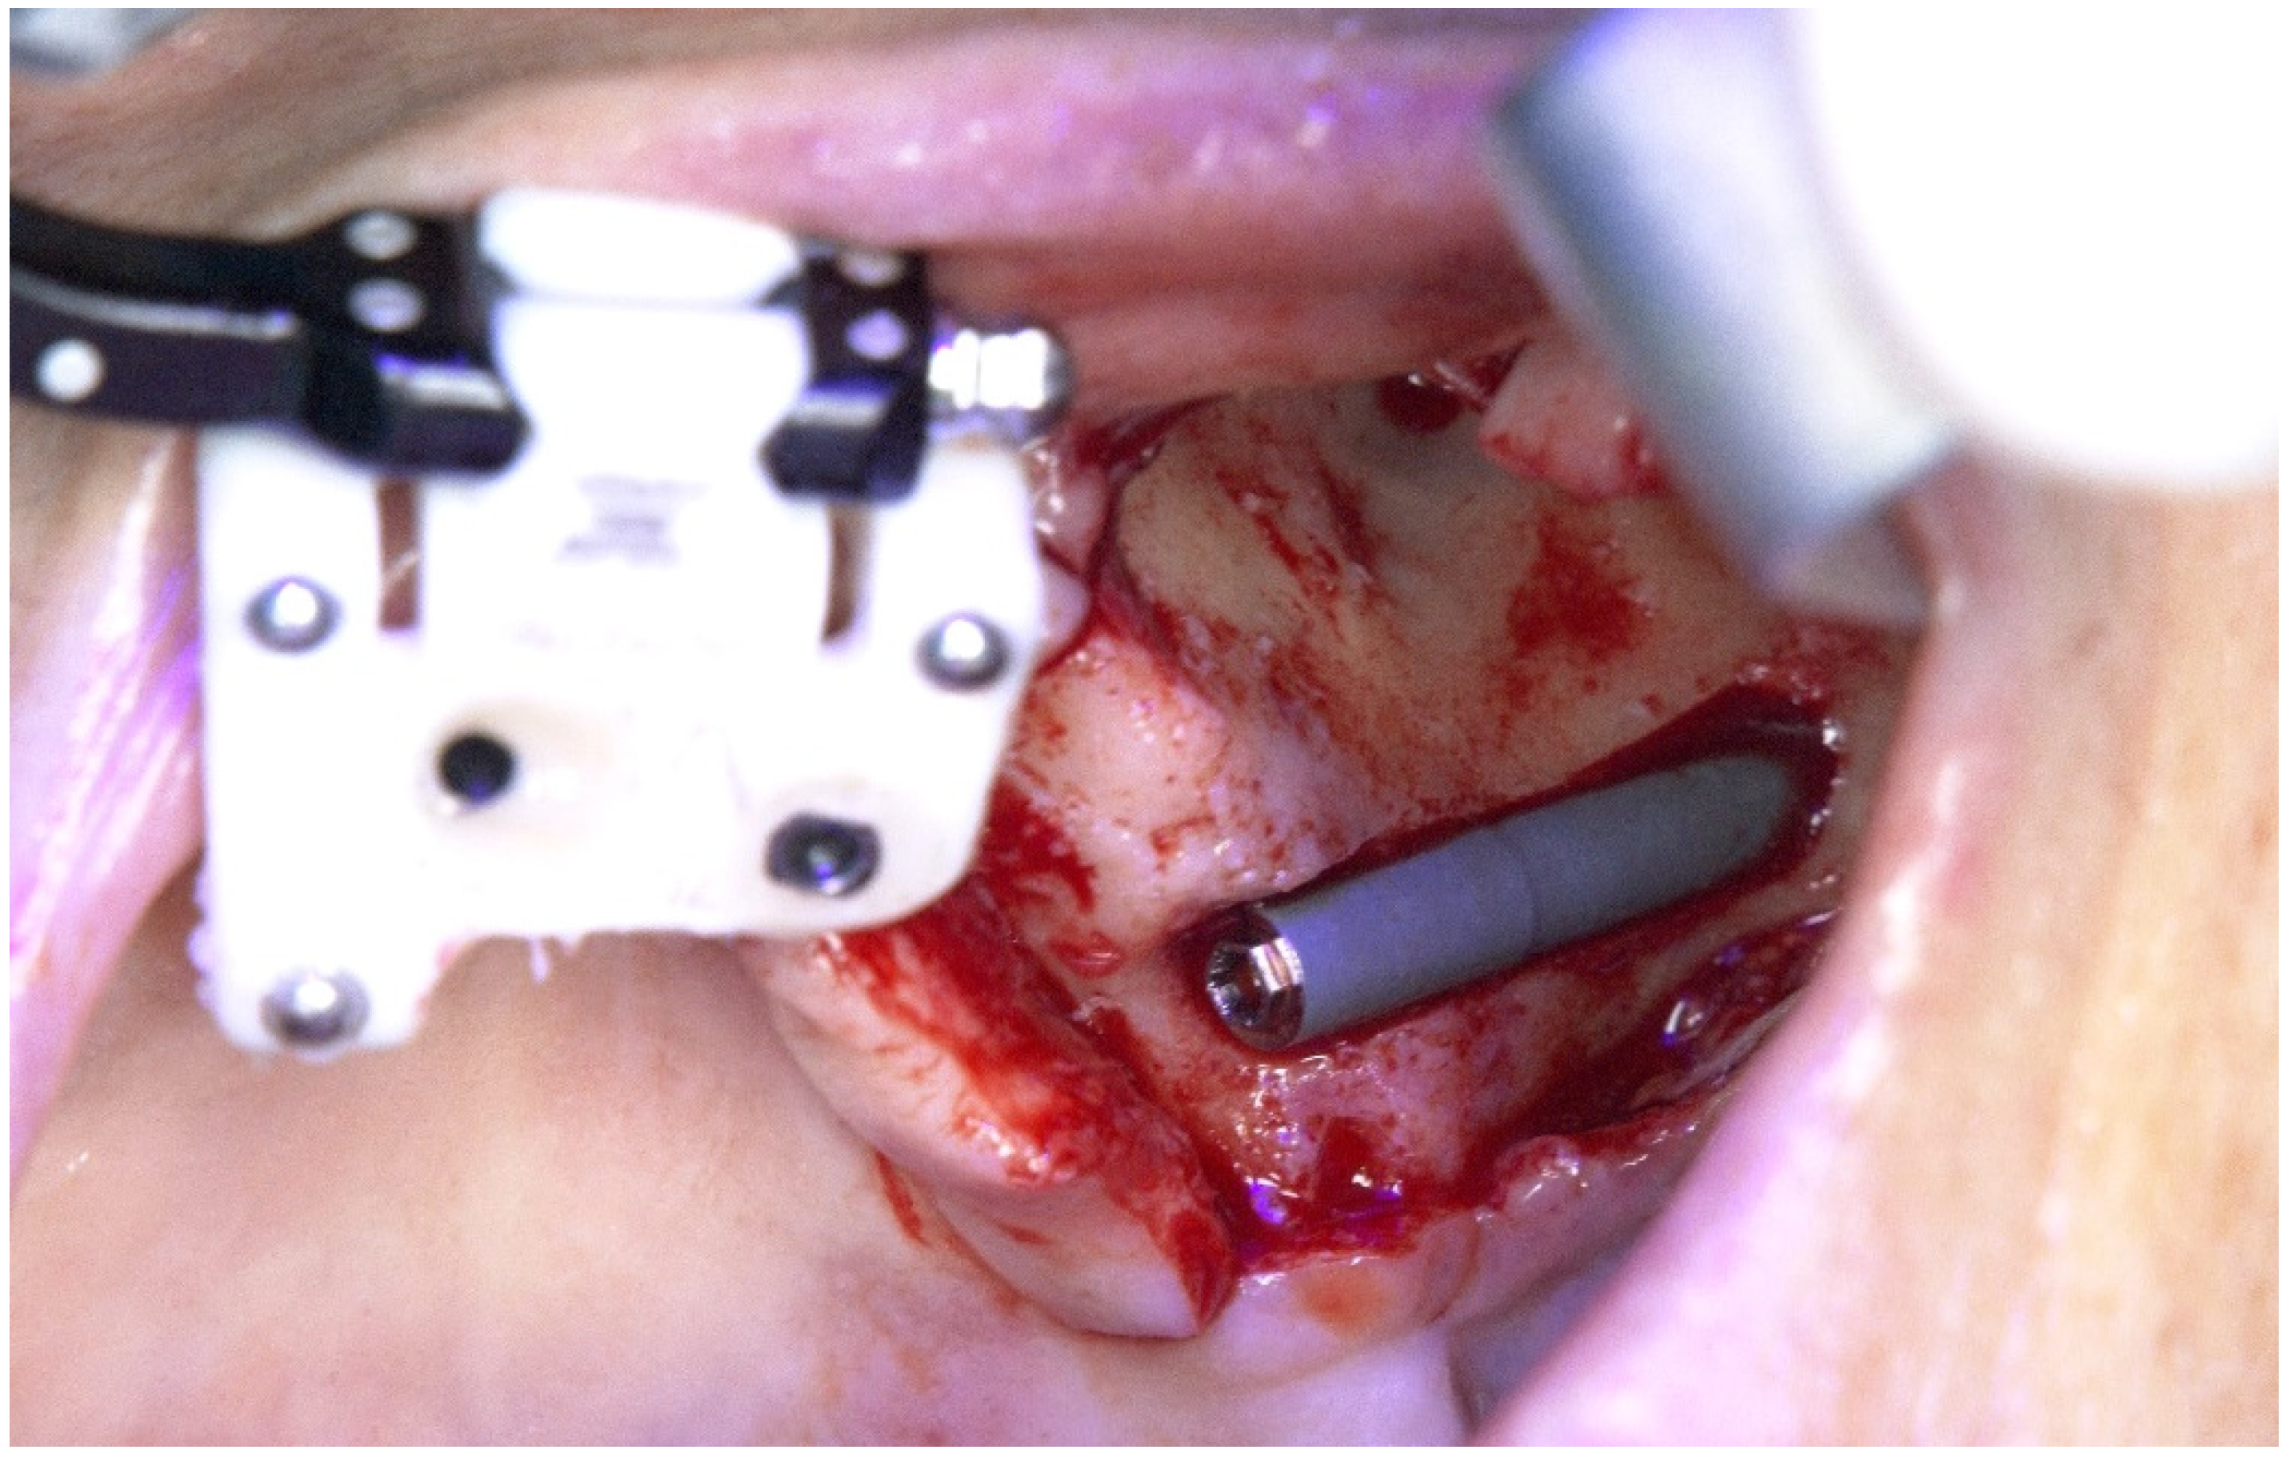

2. Case Reports

2.1. Patient 1

2.2. Patient 2